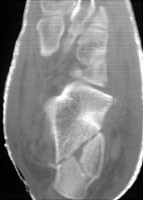

D | Axial CT. This image better demonstrates the comminuted calcaneal fracture. |